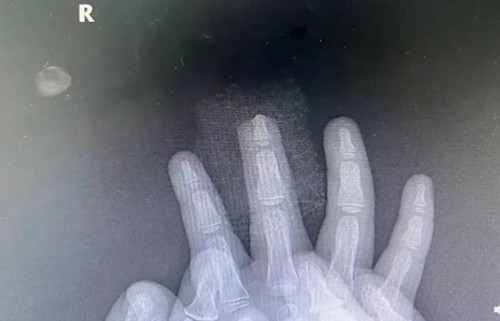

| Bé gái bị kẹp đứt ngón tay giữa do nghịch cánh cửa khi cha mẹ không để ý. |